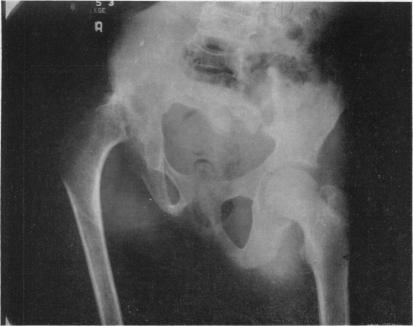

The bone changes in sickle cell anaemia.

Ann R Coll Surg Engl. 1956 Nov;19(5):296-315.